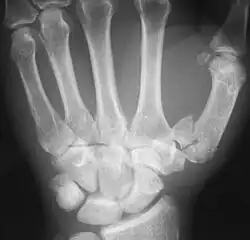

Bennett-Fraktur im Röntgenbild

Bei der Bennett-Fraktur (auch Bennett-Luxationsfraktur) handelt es sich um eine Fraktur an der Basis des ersten Mittelhandknochens, die bis in das Daumensattelgelenk zieht. Der Mittelhandknochen wird durch den Zug der hier ansetzenden Sehne des M. abductor pollicis longus nach proximal verschoben. Meist bleibt ein kleineres dreieckiges Fragment ulnar am Gelenk stehen.